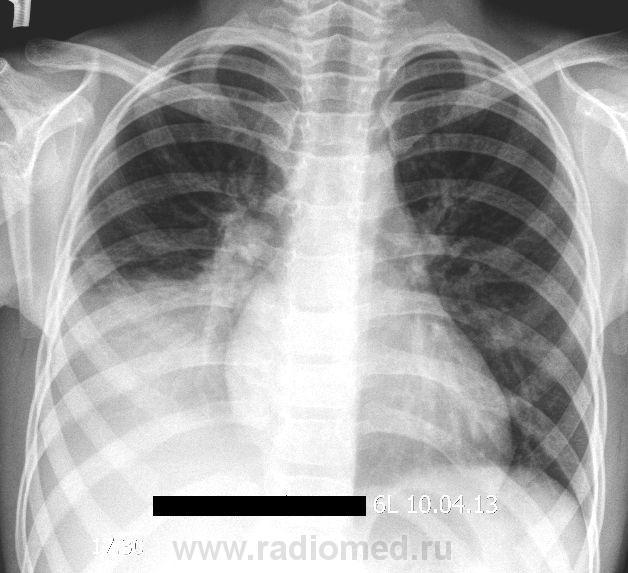

Девочка 6 лет. Болеет 7дней, повышение температуры до 39, кашель. К врачу не обращались, лечились домашними средствами. Вчера появилась боль в правой половине грудной клетки. После выполнения снимка произведена плевральная пункция - получено около 50 мл гемолизированной крови с хлопьями и нитями фибрина.

последние 2 снимка после пункции.

Объем поражения - нижняя доля правого легкого (инфильтрация (S6-S10) на фоне усиленного легочного рисунка, корень неструктурен) с умеренный уменьшением объема доли.

Думаю, нижнедолевая пневмония (все сегменты базальной пирамиды). Боковой снимок сильно развернутый получился.

Думаю, что налицо и пневмония (в восьмерке), и выпот. Раз жидкости получили мало - осумкование и ячейки. Про УЗИ - +1, пунктировать в оптимальном месте после разметки.

А чего это просвета бронхов на фоне инфильтрации не видно? Главная междолевка немного втянута к затенению. Не было бы ателектаза (хотя смещения средостения проаво и низведения корня книзу нет). Шестерка интактна. Выпот есть, причем (мне кажется) он преимущественно и дает затенение.

Я думаю, что затемнение преимущественно, все-таки, дает инфильтрация; выпот, конечно, тоже есть, но не так много. Выраженную консолидацию без видимых просветов бронхов при долевых пневмониях у детей видела не раз на КТ.

Не видно позитивной воздушной бронхографии. При пневмонии хоть где-то должен быть бронх с воздухом. Выпот, фибринозный. Хотя за ним может быть и инфильтрация прикрыта.

2.Если имеет место ателектаз, как предполагают некоторые коллеги, то возникает вопрос, ателектаз чего?(каких сегментов?). Моё мнение, имеет место инфильтрация сегментов базальной пирамиды нижней доли.Данных за ателектаз нет, данные за выпот в плевральной полости сомниельные( в пунктате могли получить кровь).